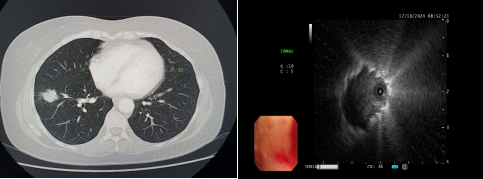

患者,女性,于10天前无明显诱因出现咳嗽,干咳为主,未予以重视,之后仍咳嗽、咳痰,就诊于外院,胸部CT提示双肺纹理增粗、右肺门团块影、右肺下叶前基底段实性结节团。为求进一步诊治转入我院MILAN.COM。入院后完善相关检查,于10月17日9时安排气管镜检查,副主任医师韩蓓与主管护师薛冬冬为患者行气管镜检查,镜下示:双肺支气管均未见明显异常,结合CT给予超声探查,于右肺下叶前基底段亚支探及偏心异常回声区,由于亚支位置较远且管腔较窄,活检钳无法到达,给予冷冻肺活检,成功获取3块活检标本,活检病理结果提示为恶性肿瘤。